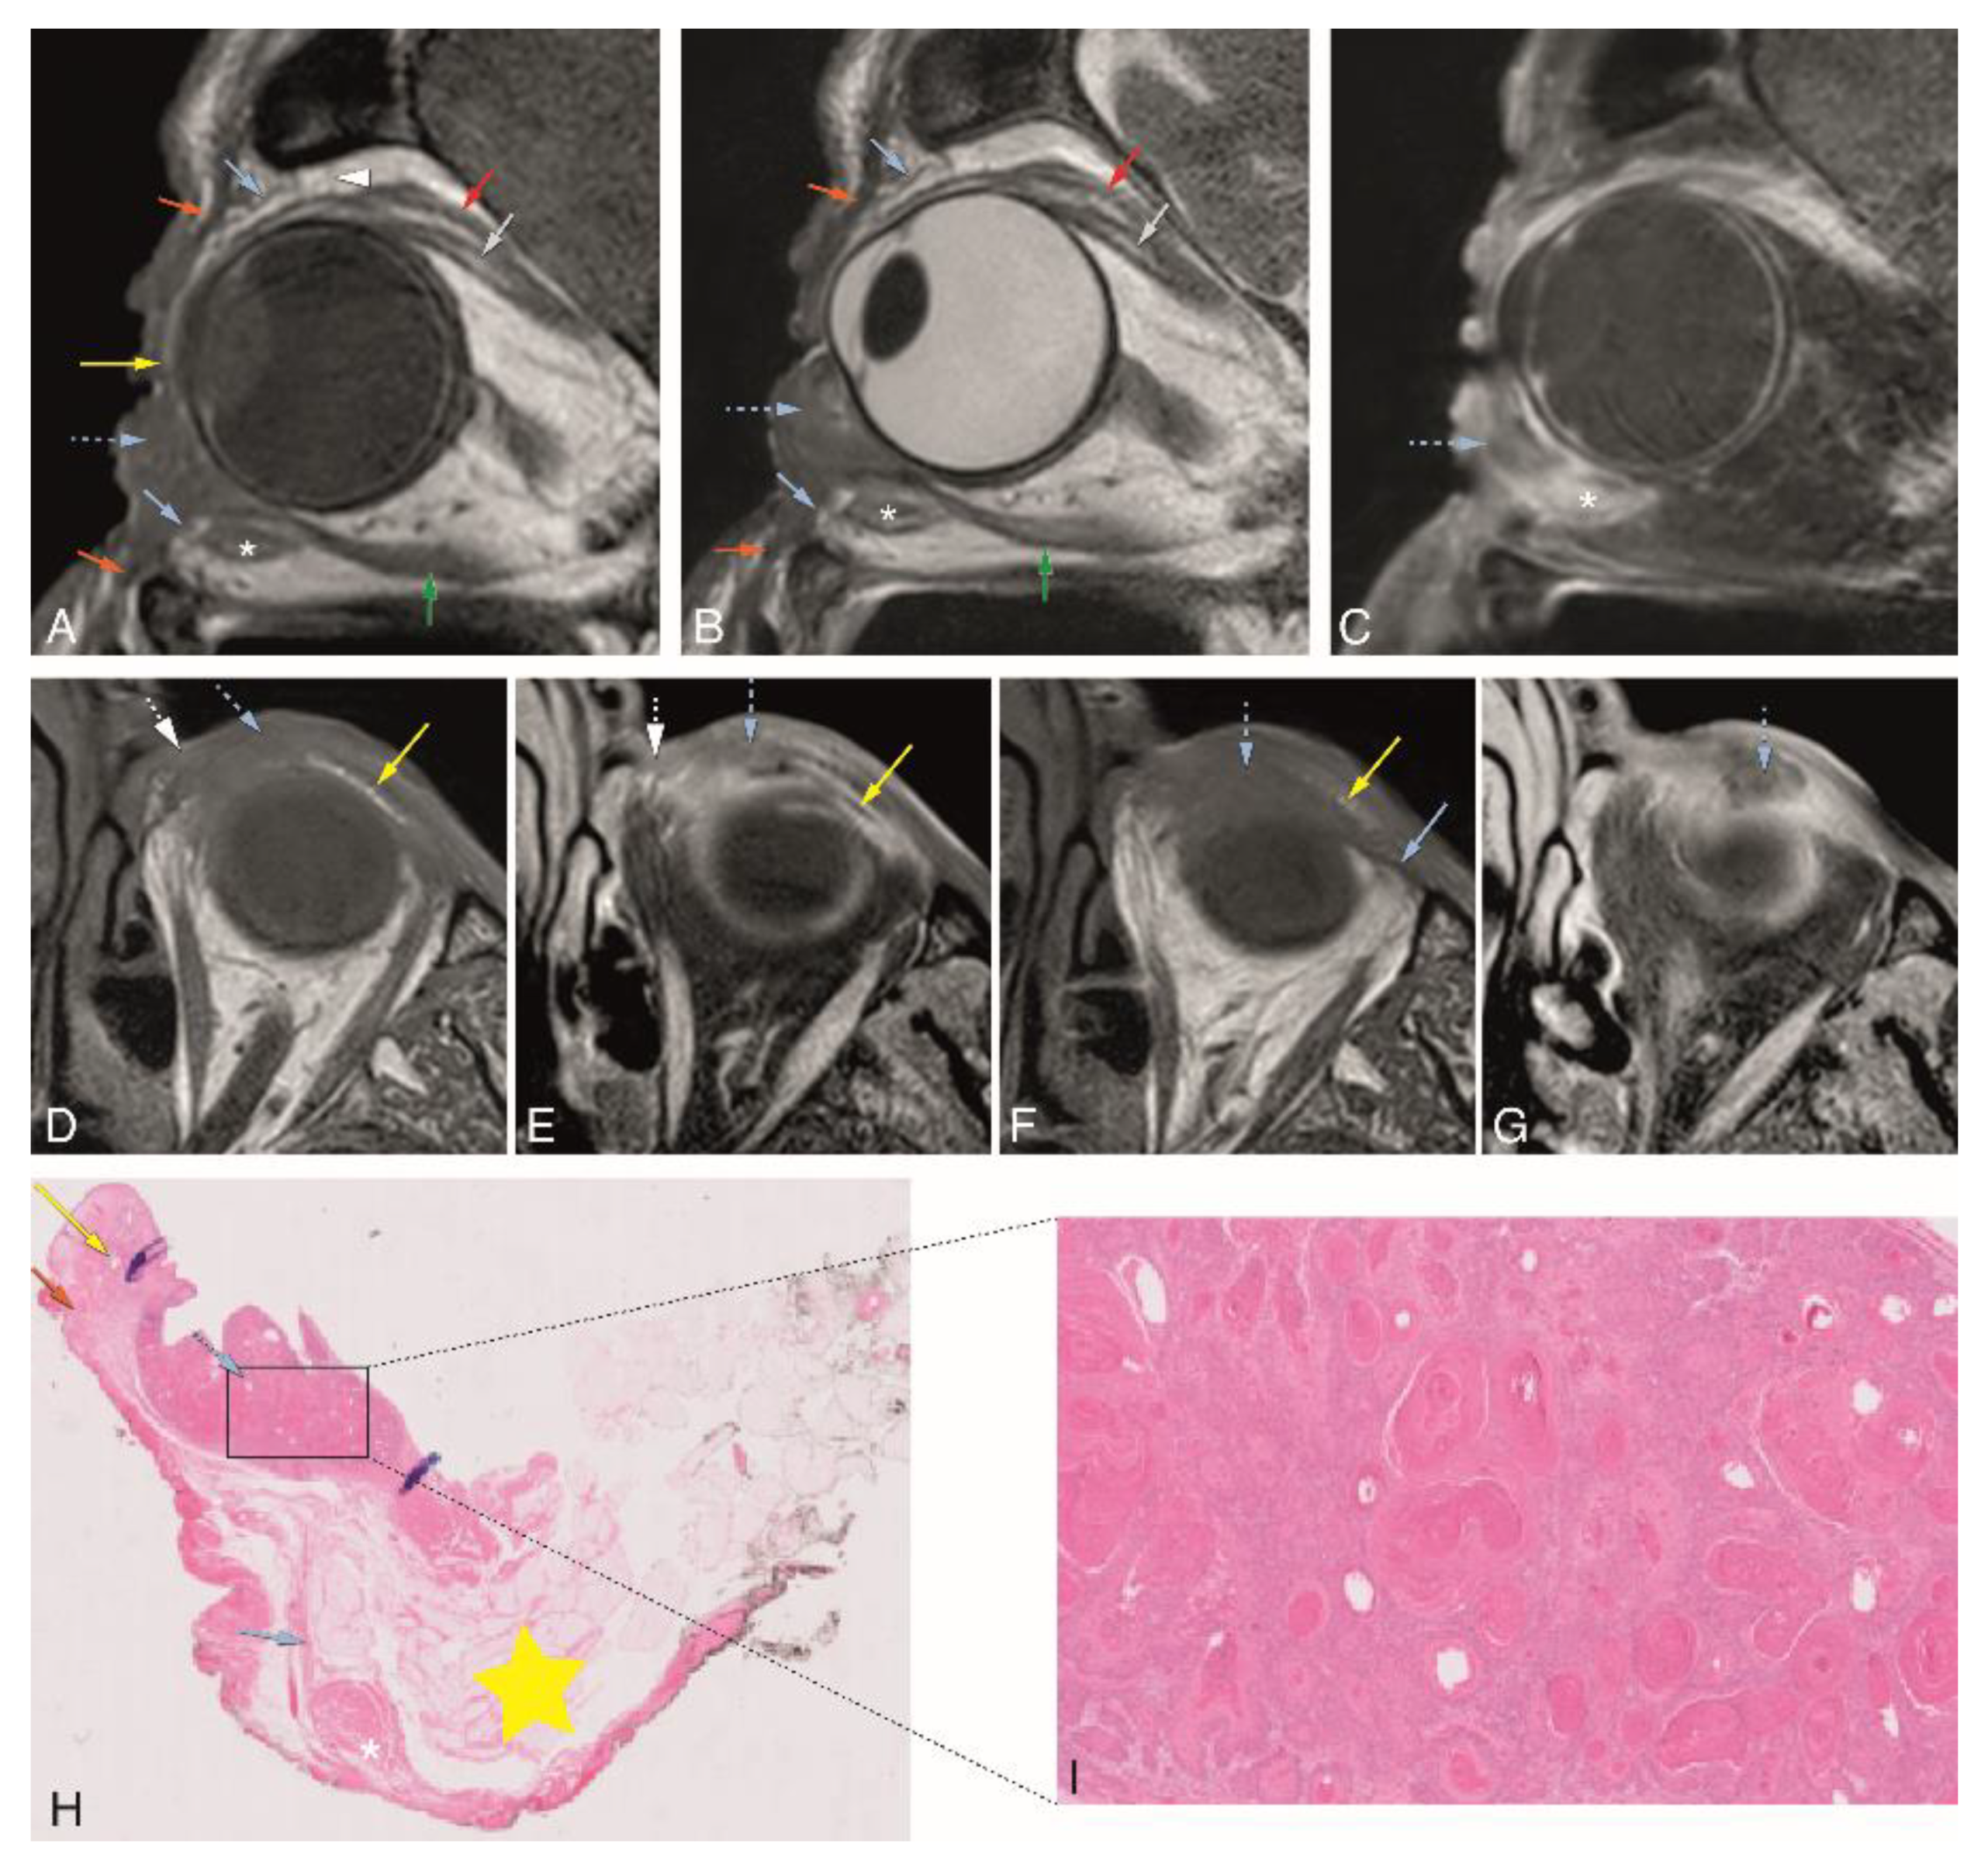

Figure 5. A–I: Patient #1 of Group 3 with a squamous cell carcinoma (SCC) of the left inferior tarsal and bulbar conjunctiva (dedicated eyelid protocol). A–C: Sagittals T1-WI (A), T2-WI (B), and contrast-enhanced T1-WI with fat signal suppression (C) showing the tumor (blue dashed arrow) invading the orbit and reaching the region of insertion of the inferior rectus muscle at the globe. D–G: Axials T1-WI (D,F) and contrast-enhanced T1-WI with fat signal suppression (E,G) at the level of the inferior eyelid (slices D and E are superior to slices F and G). Notice the tumor (blue dashed arrow) invading the medial inferior tarsal plate (yellow arrow) and medial palpebral ligament region (white dashed arrow) (D,E), and inferiorly growing behind the septum limit (blue arrow) (F,G). H–I: Histopathological examination hematoxylin and eosin stain (H&E) (0.5×) (H) and histopathological examination H&E stain (5×) (I). Notice the tumor (blue dashed arrow) at the epithelium of the palpebral conjunctiva growing anteriorly and invading the septum and posteriorly into the intraorbital fat (H). Well-differentiated SCC (I). Blue dashed arrow: tumor; orange arrow: orbicularis oculi muscle; yellow arrow: superior and inferior tarsal plates; blue arrow: superior and inferior orbital septa; white dashed arrow: medial palpebral ligament region; yellow star: intraorbital fat; white arrowhead: superior transverse ligament (Whitnall ligament); red arrow: levator palpebrae muscle; grey arrow: superior rectus muscle; white asterisk: inferior oblique muscle; green arrow: inferior rectus muscle.

In Group 3, tumor extension of 3 patients with different eyelid tumors was determined through image analysis, both on MRI and CT. The MRI of patient #1 was performed with the dedicated eyelid protocol. It showed a heterogeneous enhancing lesion of the medial aspect of the inferior eyelid on the left (Figure 5). The inferior tarsal plate (Figure 5A,B,D,F) and inferior septum (Figure 5A,B,F) were invaded, and so was the medial palpebral ligament region (Figure 5D,E). The tumor grew posteriorly, invading the orbit and reaching the region of the insertion of the inferior rectus muscle at the globe (Figure 5A–C). Due to the location of the tumor, adjacent to the medial orbital bony wall, a CT scan was also performed, but no bone invasion was noticed either on CT or on MRI. CT was able to demonstrate septal and orbital invasion as well, but underperformed compared to MRI and could not depict tarsal invasion. Due to the presence of orbital invasion, both clinically and radiologically, an eyelid-skin sparing orbital exenteration was performed. The final histopathological examination revealed a well-differentiated squamous cell carcinoma at the epithelium of the palpebral conjunctiva, growing anteriorly invading the septum and posteriorly into the intraorbital fat, surrounded by a diffuse inflammatory infiltrate. No perineural or angioinvasive extension was seen (Figure 5H,I).